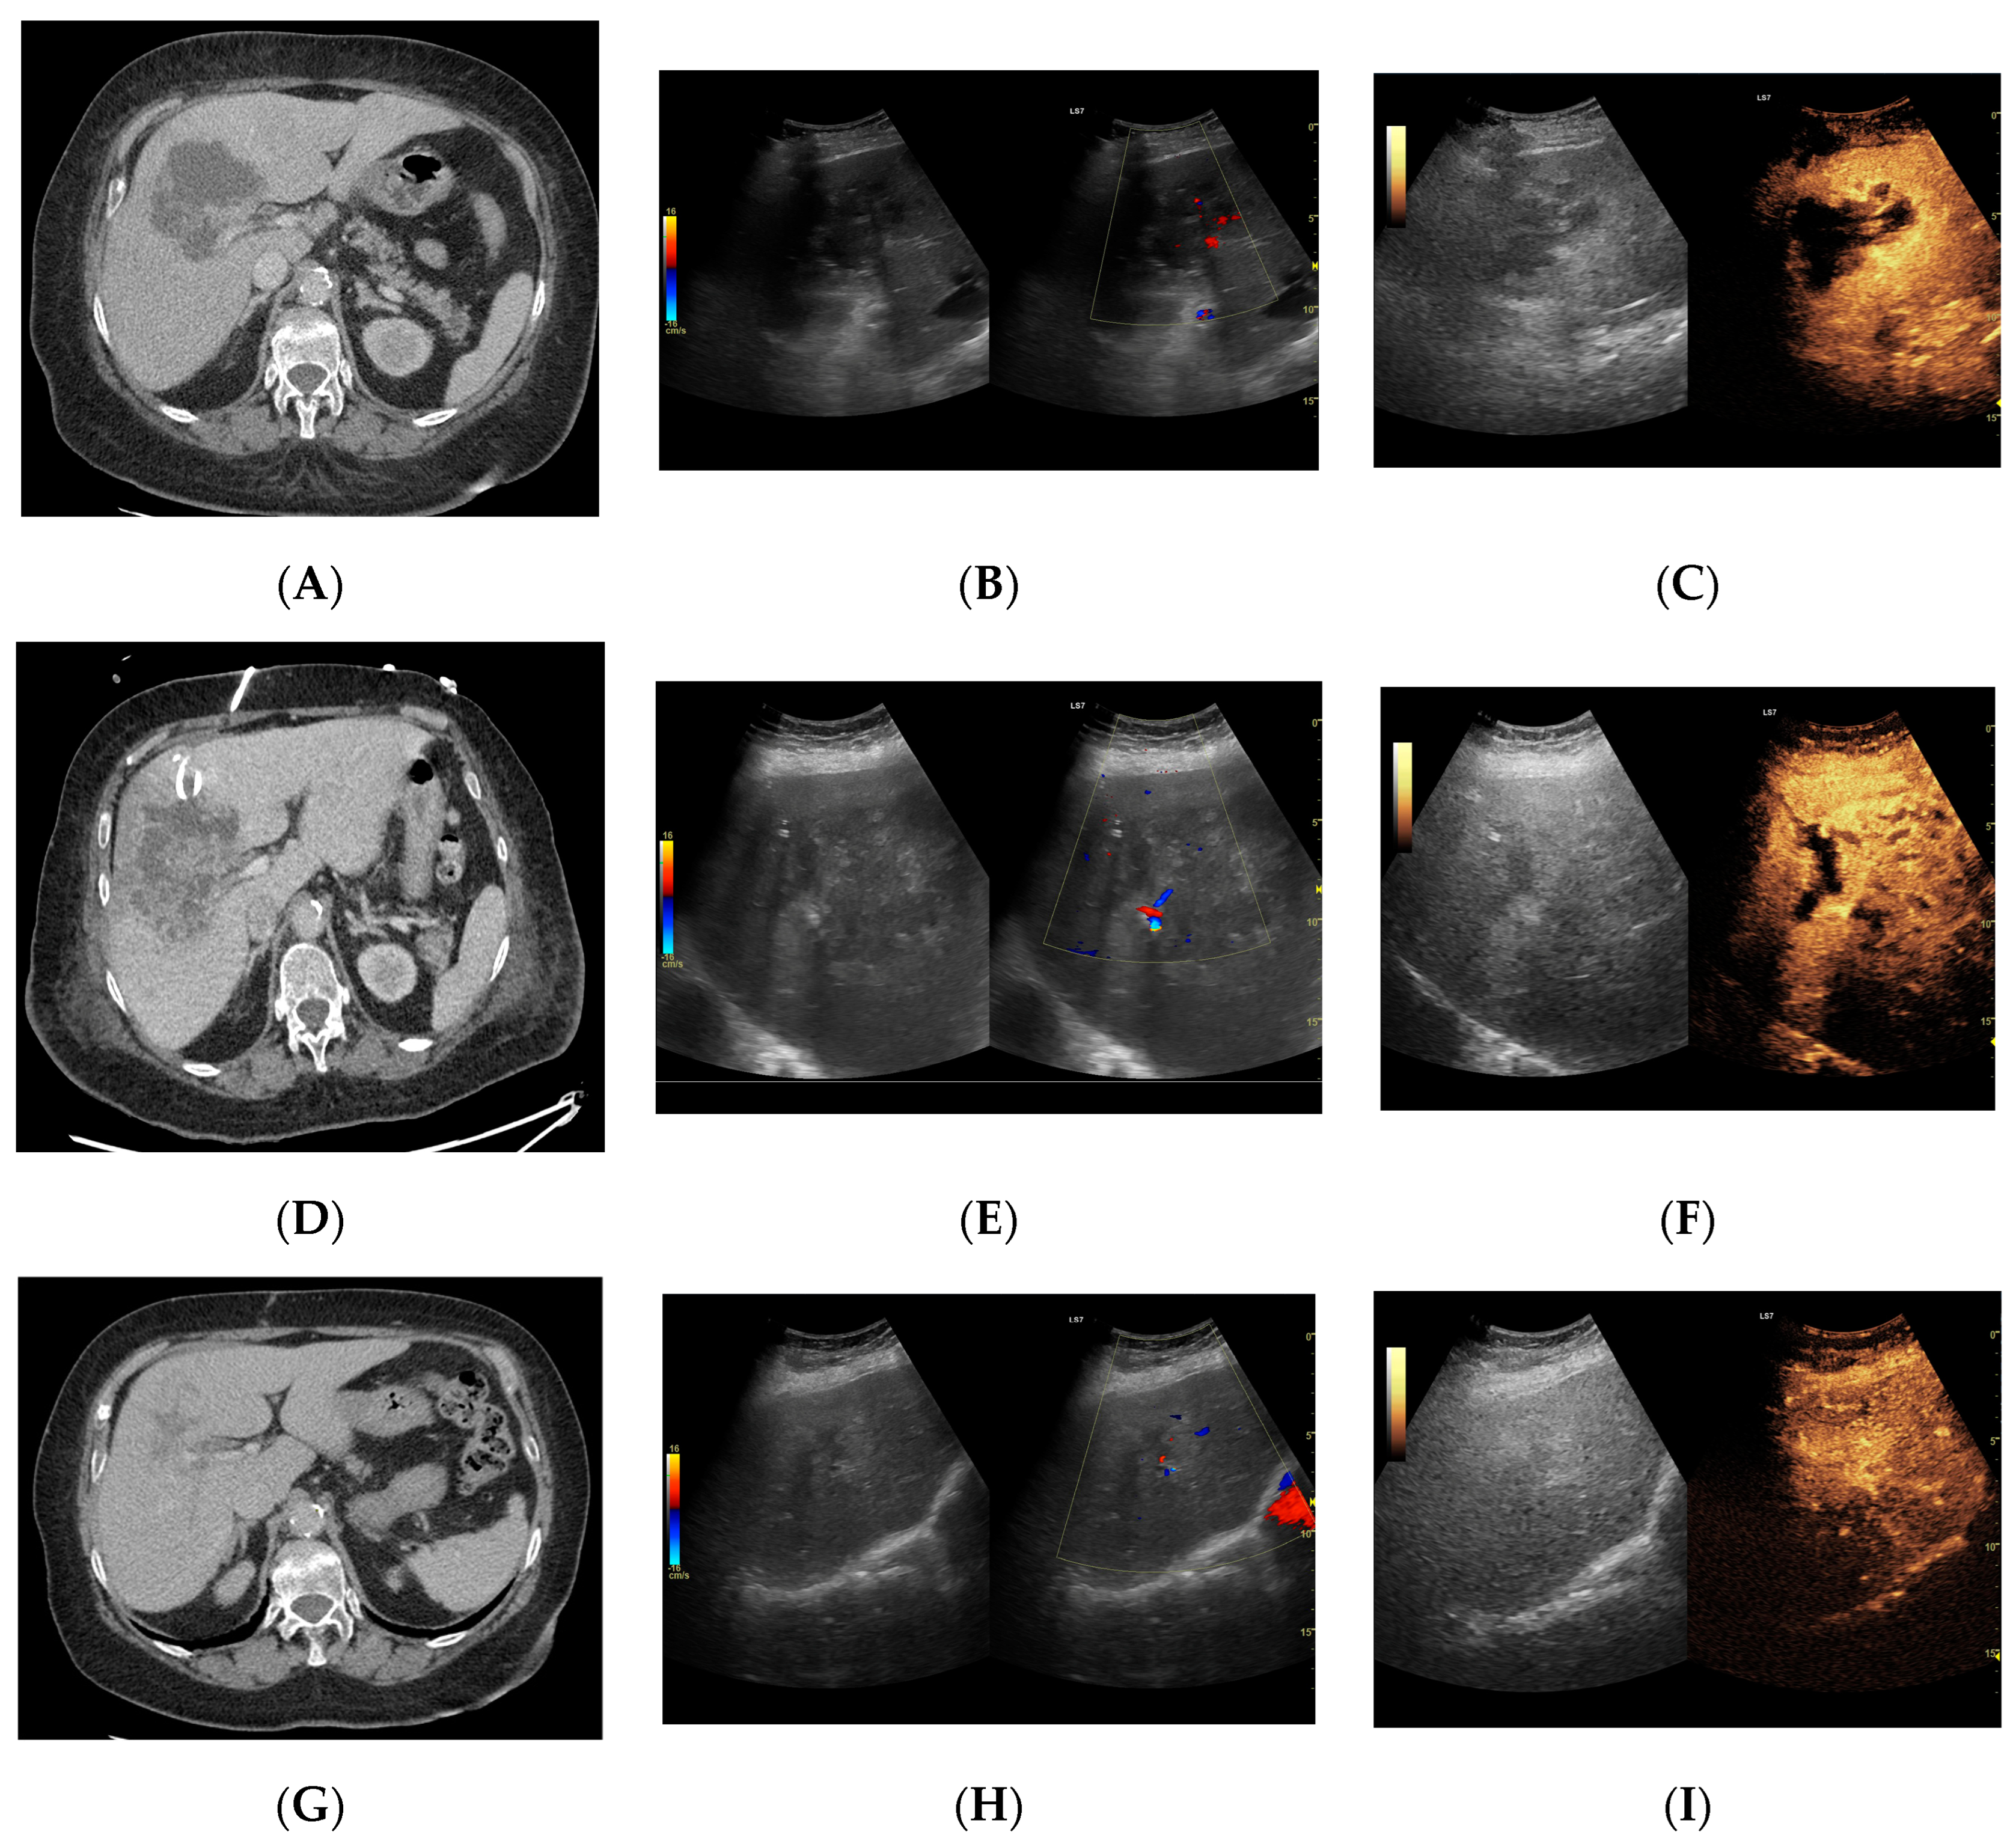

Figure 8.

Focal liver lesion diagnosed as a type III abscess. (A) Post-contrast image on CT. (B) B-mode ultrasound: the fluid component of the lesion is difficult to define. (C) CEUS: the fluid component of the lesion is visible, and the patient is qualified for percutaneous drainage. (D) Post-contrast image on CT: Follow-up examination one week after placement of drains shows a visible reduction in the fluid component. The lesion is transitioning from type III to type II, with a visible “honeycomb” sign. (E) B-mode ultrasound: the fluid component of the lesion remains challenging to define. (F) CEUS: the fluid component of the lesion is visible, indicating regression from stage III to II. (G) Post-contrast image on CT: follow-up examination performed 1.5 months after placement of percutaneous drainage reveals a visible residual lesion. (H) B-mode ultrasound: a residual lesion is visible. (I) CEUS: the residual lesion shows the fluid component to be completely invisible, with a connective tissue scar present.